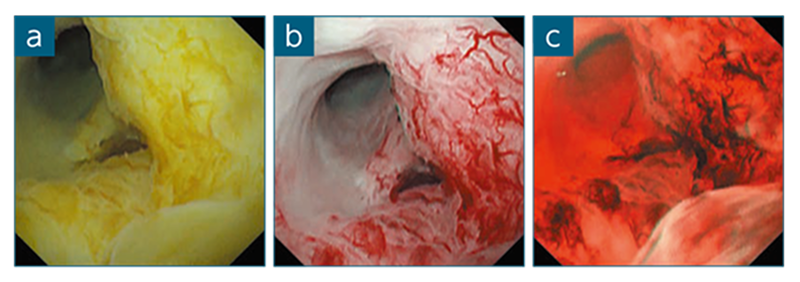

症例提示:胆嚢癌のため腹腔鏡補助下で胆嚢切除後、腹部CTにより総胆管および残存胆管に壁肥厚を認めた症例

POCSにより総胆管に扁平な隆起領域を認めたため、狭帯域光観察(NBI)に切り替えて観察したところ、悪性を示唆する異常な血管を認めたが、胆汁により視認性が不良であった。そのため、NBIからRDIモード3へ切り替え、胆汁の彩度を下げて観察することにより、異常血管に対して明確な視野を得ることが可能となった(図3)。

図3 POCSにより総胆管の扁平隆起を観察:NBI(a)、RDIモード3(b)

症例提示:体重減少を主訴とし、MR胆管膵管撮影(MRCP)およびERCPにより総胆管門脈に複数の狭窄を認めた症例

本症例はIgG4関連硬化性胆管炎(IgG4-SC)が疑われたが、血清レベルおよびIgG4レベルが標準範囲内であり、腫瘍マーカの増加もわずかであったため、POCSによる確認が行われた。RDIモード1では表層の血管を十分に確認できなかったが、RDIモード3を使用することにより拡張した血管を認め(図4)、悪性腫瘍である可能性が考慮されたが、遠位端に粘膜下腫瘍(SMT)様の領域が確認され、IgG4-SCに近い良性腫瘍であることが示唆された。RDIモード1を使用して総胆管肺門部狭窄から生検を採取し、病理学的検査を行った結果、悪性所見は得られなかったもののIgG4陽性リンパ球の集簇を認め、最終的にIgG4-SCと診断された。本症例は胆管へのステント留置後1ヵ月のフォローアップ時に狭窄の顕著な改善を認めており、IgG4-SCの診断結果と一致した経過を示した。

図4 POCSにより総胆管の表層血管を観察: RDIモード1(a)、RDIモード3(b)、NBI(c)